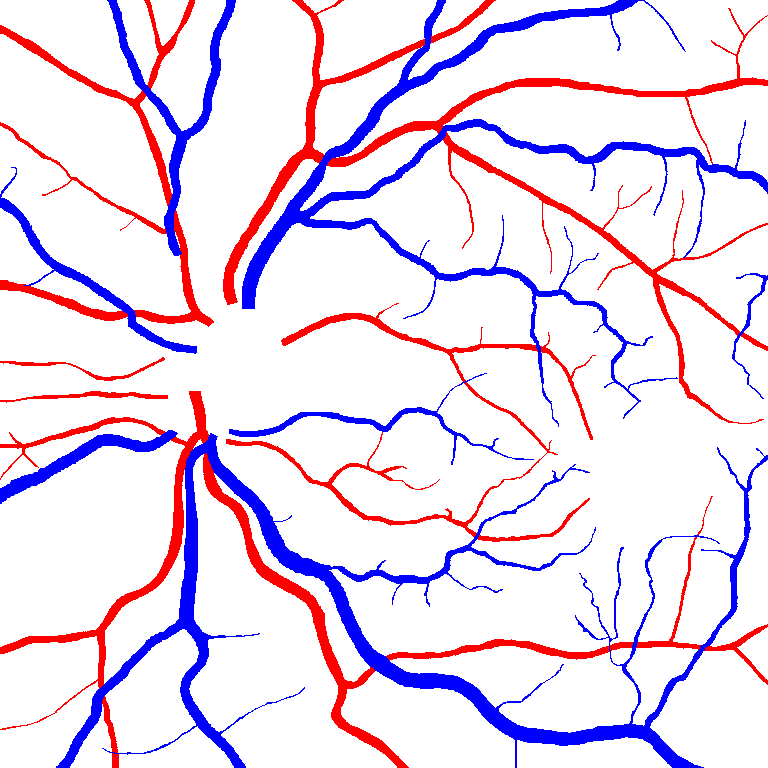

VI-B Vessel Width Estimation

Table VI presents a quantitative comparison of the measured diameters using the segmentation outputs of SegRAVIR and competing approaches. Using the pixel-wise annotated masks, the reference average diameter of the arteries and veins in the test set of the RAVIR dataset were measured as and , respectively. According to our analysis, SegRAVIR can accurately measure the diameter of the vessels and it achieves the smallest MAPE among the competing approaches. Specifically, in comparison to CE-Net, Iter-Net, and DU-Net, respectively, SegRAVIR is on average , and more accurate in terms of MAPE for the measured diameter of arteries and , and in terms of MAPE for the measured diameter of veins. Fig. 6 presents qualitative comparisons of reference and SegRAVIR estimated diameter maps.

(a) (b) (c)